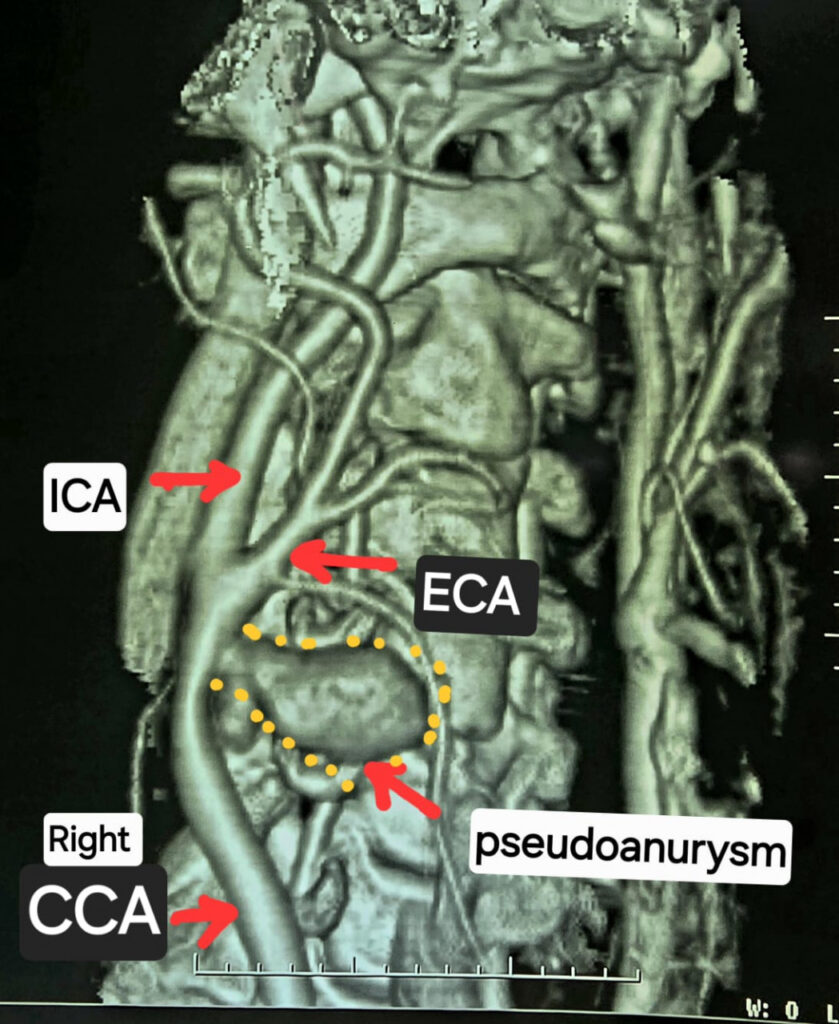

सीटी एंजियोग्राफी से हुआ दुर्लभ बीमारी का खुलासा

जांच के दौरान गर्दन की नसों की सीटी एंजियोग्राफी कराई गई, जिसमें पता चला कि मरीज की दायीं कैरोटिड आर्टरी स्वतः फट चुकी है। धमनी के आसपास गुब्बारे जैसी संरचना बन गई थी, जिसे कैरोटिड आर्टरी स्यूडोएन्युरिज्म कहा जाता है। स्थिति की गंभीरता को देखते हुए मरीज को तत्काल हार्ट, चेस्ट एंड वैस्कुलर सर्जरी विभाग में वरिष्ठ सर्जन डॉ. कृष्ण कांत साहू के पास रेफर किया गया।